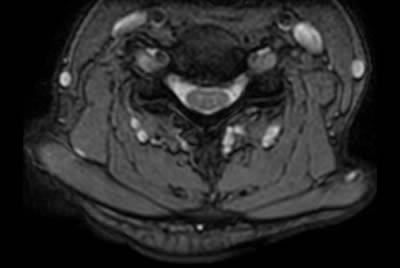

Prostate with dual coil set-up

-